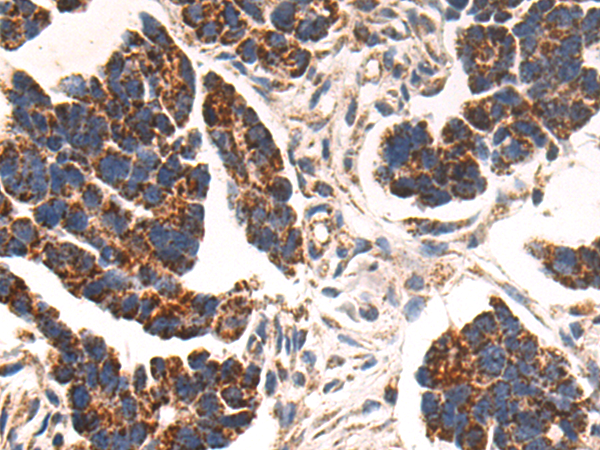

分类: 科研抗体货号: P08266别名: EF2; EF-2; EEF-2; SCA26应用: WB,IHC反应种属: Human, Mouse, Rat